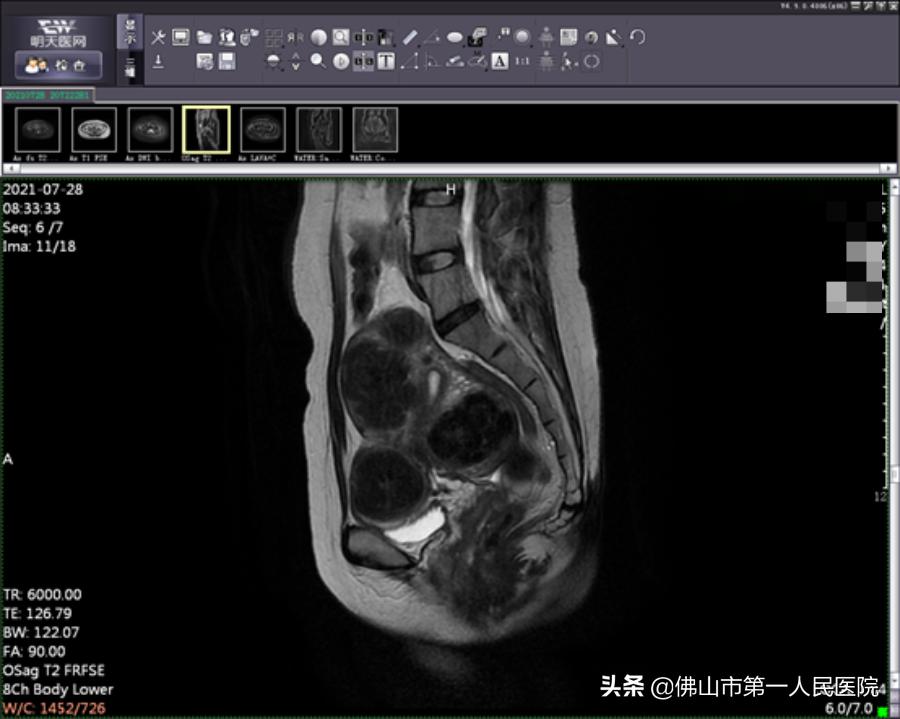

术前图像

经充分检查和术前评估,陆女士符合“海扶刀”治疗指征。由于陆女士子宫肌瘤分布于于肌壁间、黏膜下和浆膜下,数量较多,大小不一,我院海扶中心潘智茵副主任及其团队结合多年“海扶刀”治疗经验,制定了宫腔镜检查联合“海扶刀”手术的治疗方案。

2021年7月,医生为陆女士行宫腔镜检查,子宫内膜未见明显异常,粘膜下肌瘤向宫腔凸起小于二分之一,大于二分之一位于肌壁间。宫腔镜检查术后1天患者无明显阴道流血,遂行海扶刀手术。